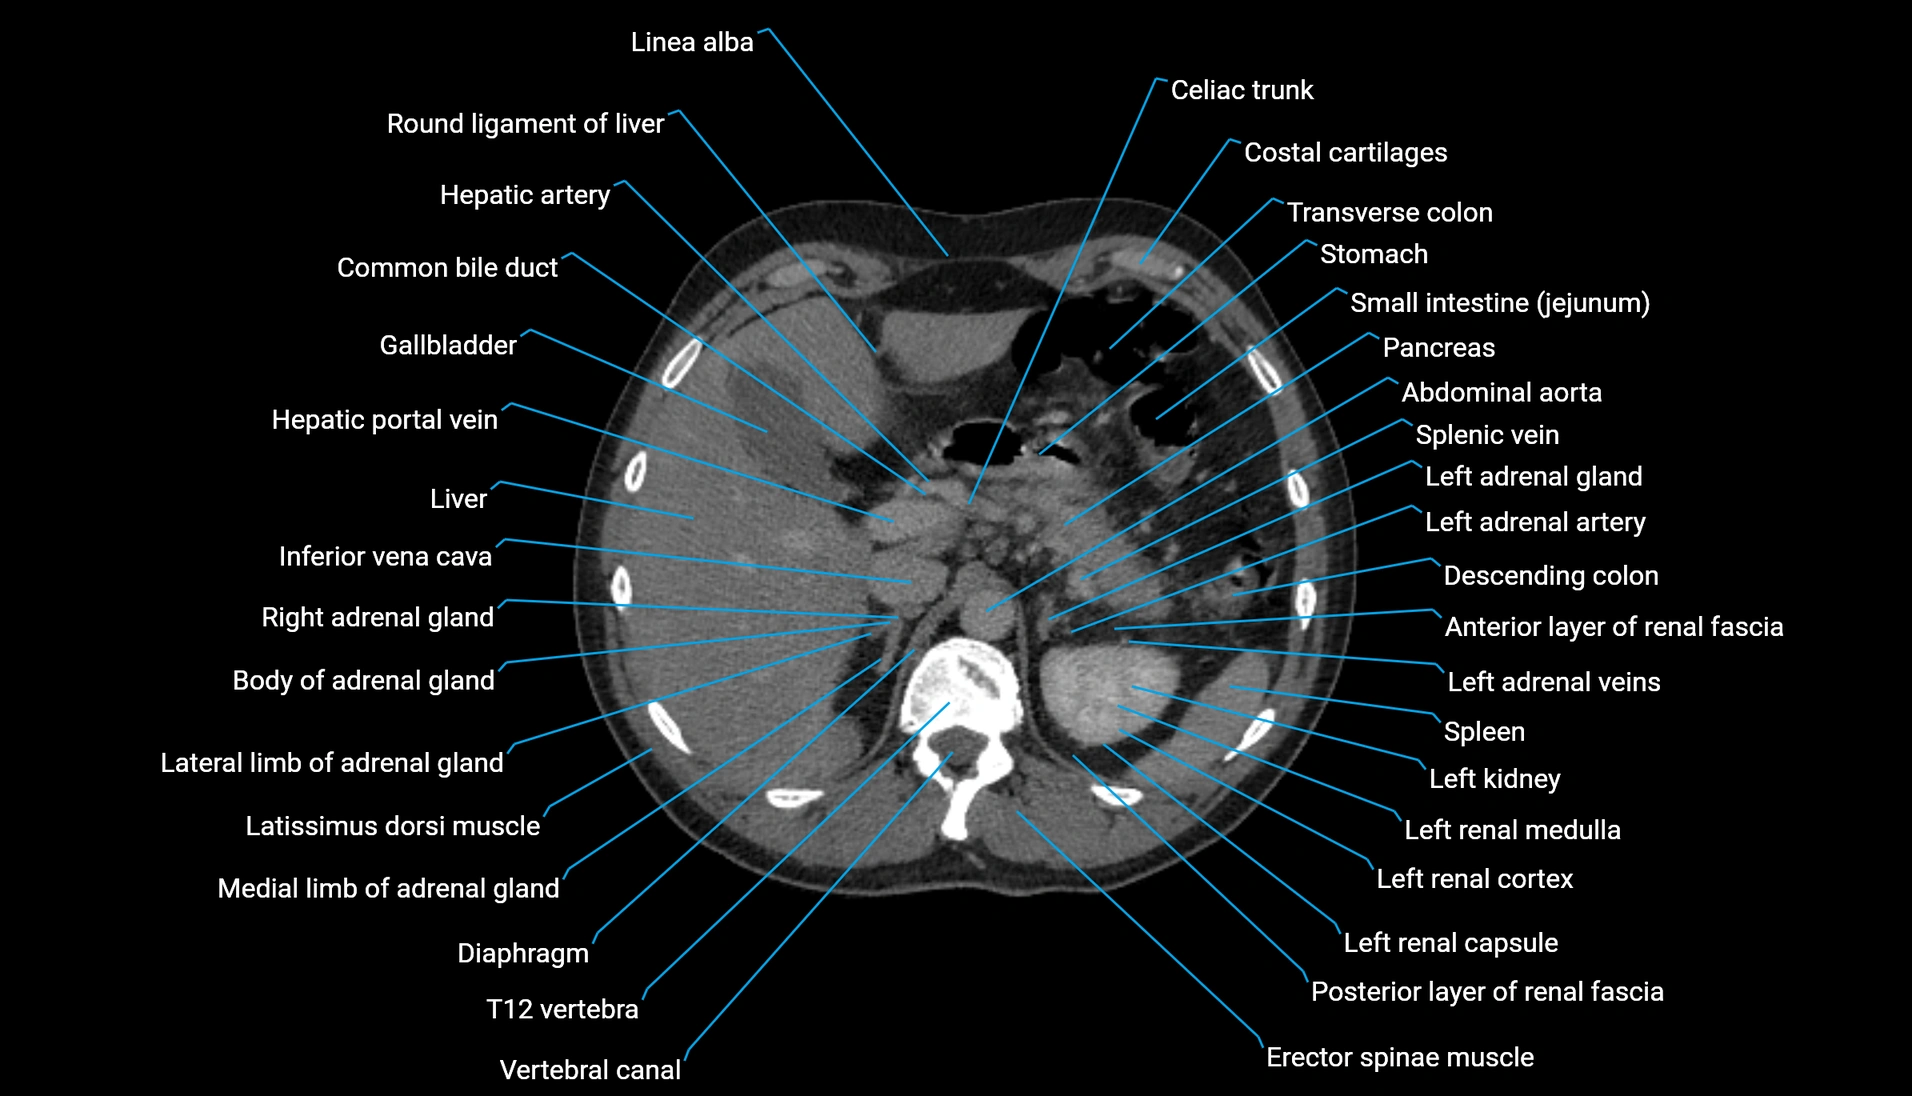

CT Appearance

Non-contrast CT:

-

Demonstrates cortical bone of acetabular rim in excellent detail

Detects fractures, dysplasia, retroversion, or bony overcoverage (pincer impingement)

3D reconstructions used in preoperative hip surgery planning

CT VRT 3D image

CT image